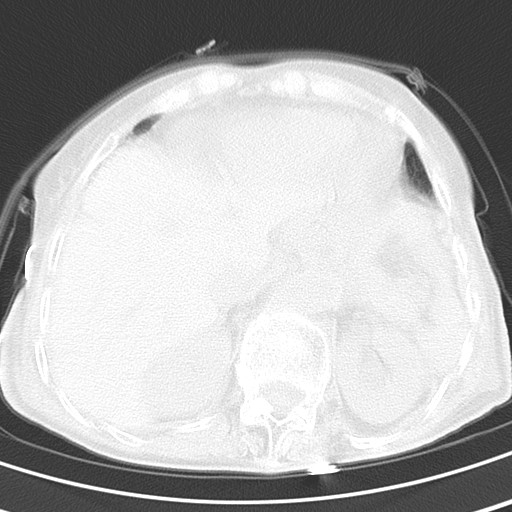

标题: CT21467:女,93岁,摔伤后检查。

女,93岁,摔伤后检查。

食管裂孔疝

创伤性湿肺,双侧胸腔积液。可能有食管裂孔疝,进一步检查。骨折有无根据自己的机器及片子再仔细看吧。

右侧锁骨\\肩胛骨骨折、右侧湿肺,心功能不全伴双侧胸腔积液,右下肺膨胀不全,左膈破裂或食管裂孔疝,冠脉钙化,心包少量积液,请上传骨窗.